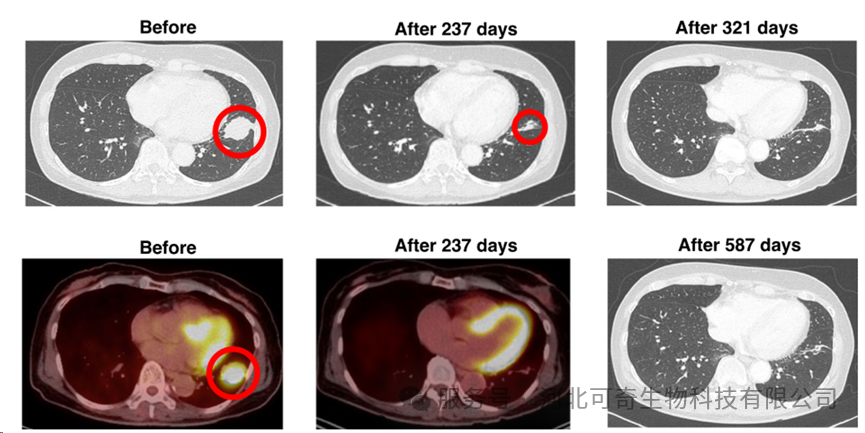

患者肺的CT和PET-CT结果

治疗效果经过 237 天的联合治疗,肿瘤大小缩小至 12 毫米,降幅达 65.7%。更值得关注的是,321 天后的 CT 扫描未发现肿瘤,即便随访至 699 天,患者仍无复发或转移迹象。且治疗全程耐受性良好,未出现相关不良事件。